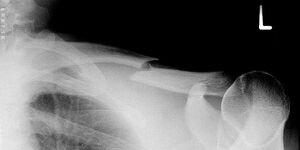

Gebrochenes Schlüsselbein - Erik Streb commons.wikimedia.org, CC BY-SA 3.0

Ein Schlüsselbeinbruch ist häufig die Folge von einem Sturz oder Schlag gegen das Schlüsselbein oder die Schulter, zum Beispiel beim Reiten, Fußball oder Skifahren. Dabei kann die bandartige Verbindung vom Schlüsselbein zum Schultergelenk reißen oder das Schlüsselbein brechen. Oft entsteht als Folge eine starke Schwellung und häufig ist eine Stufenbildung in der Schulter sichtbar.

In den meisten Fällen wird nach der Bruchversorgung für mehrere Wochen ein Rucksackverband angelegt. Krankengymnastische Übungen unterstützen die Heilung. Die Sportfähigkeit ist erst nach Ausheilung des Bruches und Beschwerdefreiheit gegeben.

Eine Operation erfolgt meist nur bei besonderen Bruchformen.